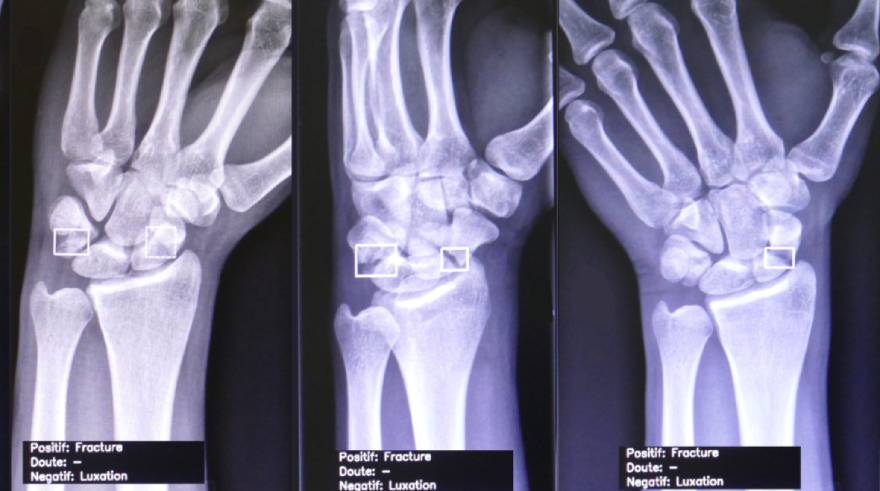

El Servicio de Diagnóstico por la Imagen ha instalado un asistente de inteligencia artificial para el análisis de imagen radiológica que permitirá mejorar la precisión de los diagnósticos. "Este software de inteligencia artificial está especializado en el análisis de las imágenes radiológicas de fracturas óseas y de patología de tórax, como derrames pleurales, nódulos, fracturas costales, neumotórax o consolidaciones y está pensado especialmente para su utilización en Urgencias", explica el Dr. Vicente Martínez de Vega

, jefe del Servicio de Diagnóstico por la Imagen del Hospital Universitario Quirónsalud Madrid. "Un radiólogo experto en fracturas tiene una sensibilidad del 93%. El software que estamos utilizando -desarrollado por la empresa Arterys- posee una sensibilidad similar a un radiologo experto y superior a un médico no formado específicamente en el análisis radiológico".

¿Cómo es el proceso de análisis? Cuando el paciente se somete a la radiografía en Urgencias, la imagen se envía a un servidor específico en inteligencia artificial que, en apenas dos minutos, analiza la imagen y ofrece tres tipos de respuestas: ausencia de patología, imagen con duda diagnóstica (en la que sería necesario consultar con un radiólogo) o imagen patológica donde marca la zona afectada y la patología sospechosa.

"El software es de gran utilidad para el Servicio de Urgencias porque nos apoya en el diagnóstico de patologías en las que podemos tener dudas", amplia Harold García Fernández, coordinador médico de Urgencias del Hospital Universitario Quirónsalud Madrid. "Desde que lo utilizamos se agilizan las decisiones con los pacientes y nos ofrece más seguridad sobre todo en el caso de pequeñas fracturas o fisuras que nos era complicado identificar. En el área de tórax los médicos de Urgencia están perfectamente preparados para el diagnóstico de cuadros de neumonía, derrames pleurales o nódulos pulmonares, pero siempre ayuda que un programa apoye lo que observamos".